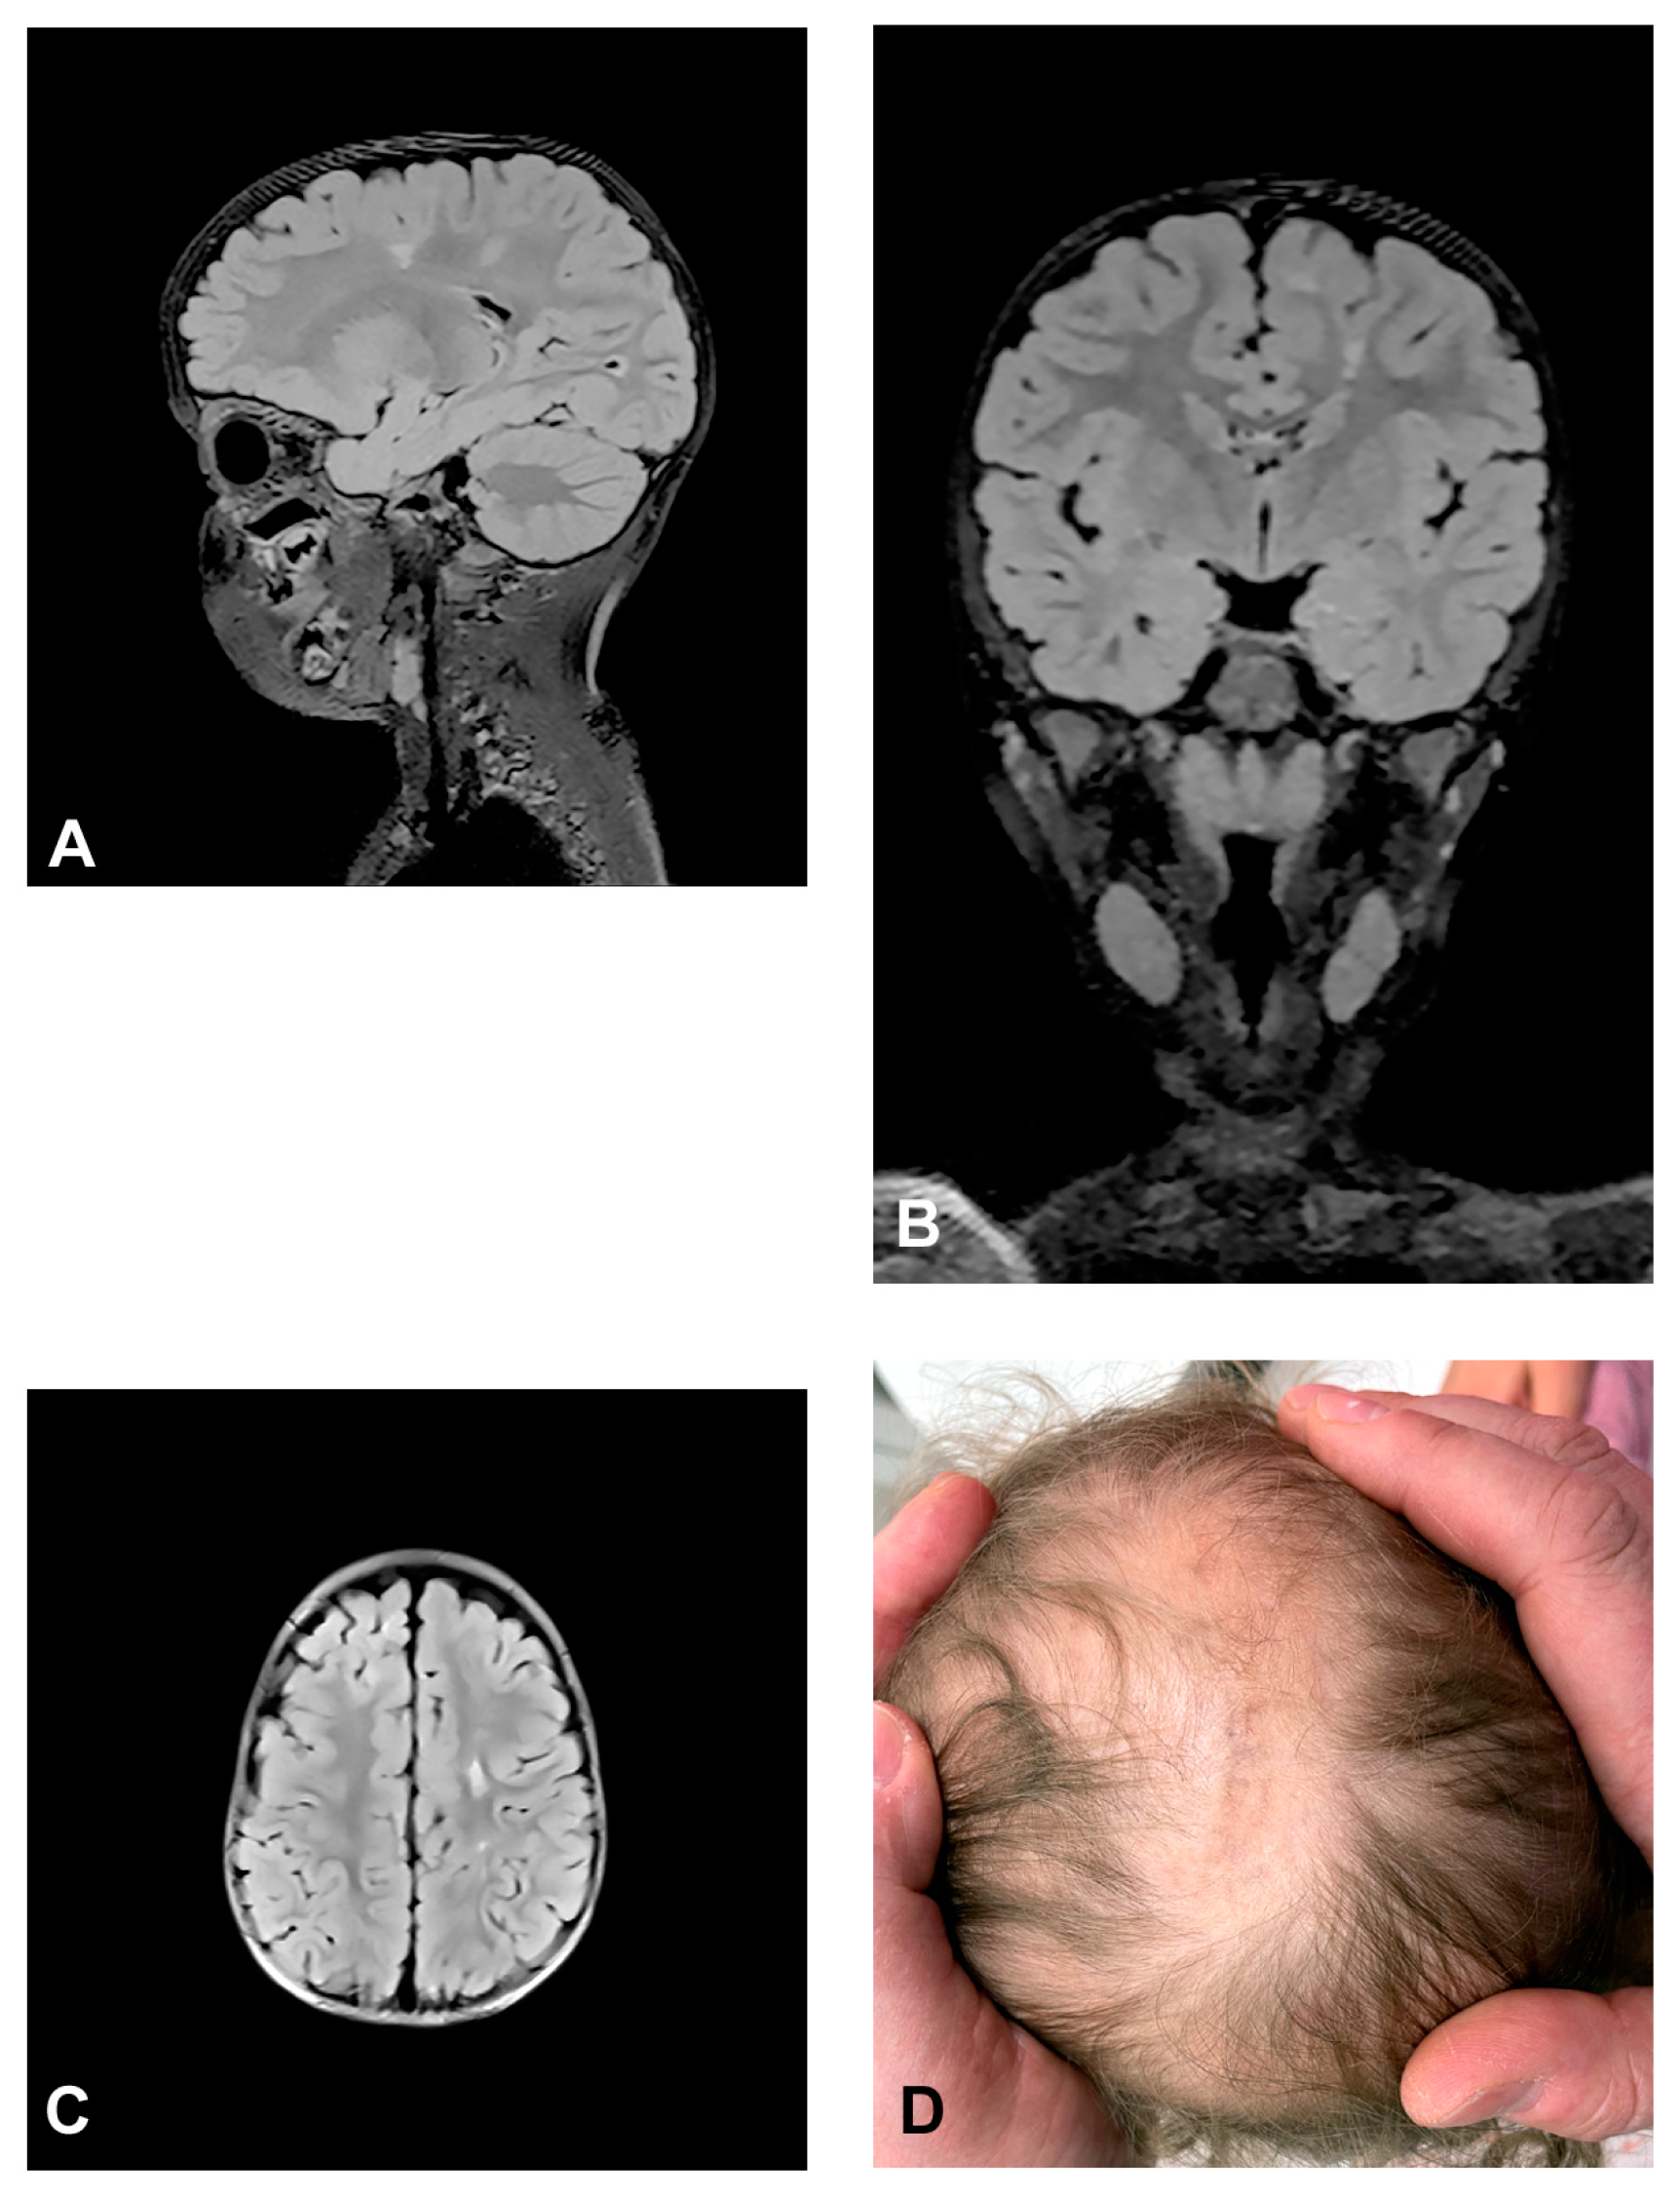

3.2.1. Case 1

3.2.2. Case 2